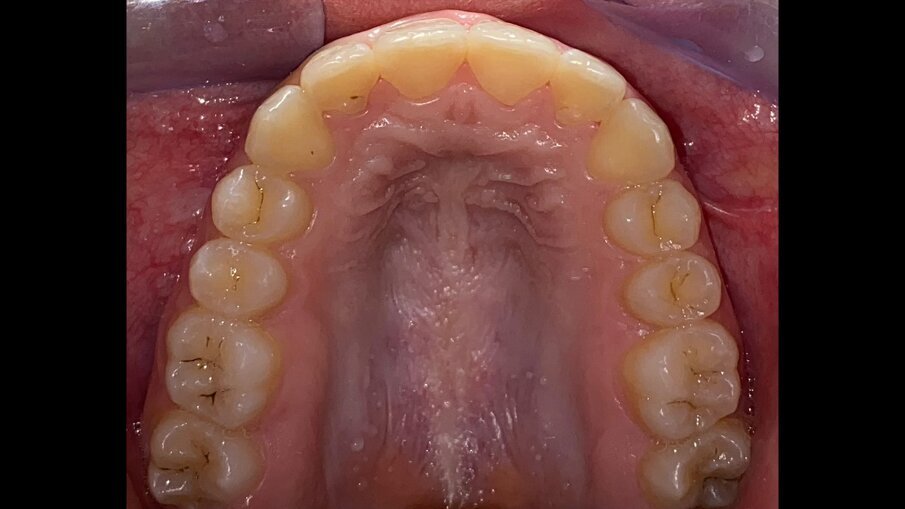

All’esame obiettivo intraorale si riscontra sul piano frontale un severo morso profondo con precontatto traumatico degli incisivi superiori contro la papilla retroincisiva e le rughe palatine anteriori durante la massima intercuspidazione, con overbite di 10 mm (Fig. 5). Dalle foto laterali si evidenzia una malocclusione di Classe II divisione 2 con scissor bite dell’elemento 1.5 (Figg. 6, 7), mentre dalle foto occlusali si rileva un grave affollamento con contrazione di entrambe le arcate maggiore nella zona premolare (Figg. 8, 9). L’analisi di Bolton mostra un eccesso superiore 3-3 di 2,34 mm (73,6%) e 6-6 di 2,76 mm (88,8%). L’analisi cefalometrica evidenzia una Classe II scheletrica, modello facciale normodivergente, angolo interincisale aumentato, incisivi superiori e inferiori retroinclinati (Fig. 10). La radiografia panoramica mostra la presenza dei germi dei terzi molari, assenza di parallelismo tra le radici dei premolari inferiori (Fig. 11) e una sovraeruzione degli incisivi inferiori che crea un doppio piano tra gli incisivi e i molari, segno di una curva di Spee molto profonda.

Fig. 8_Occlusale superiore pre-trattamento.